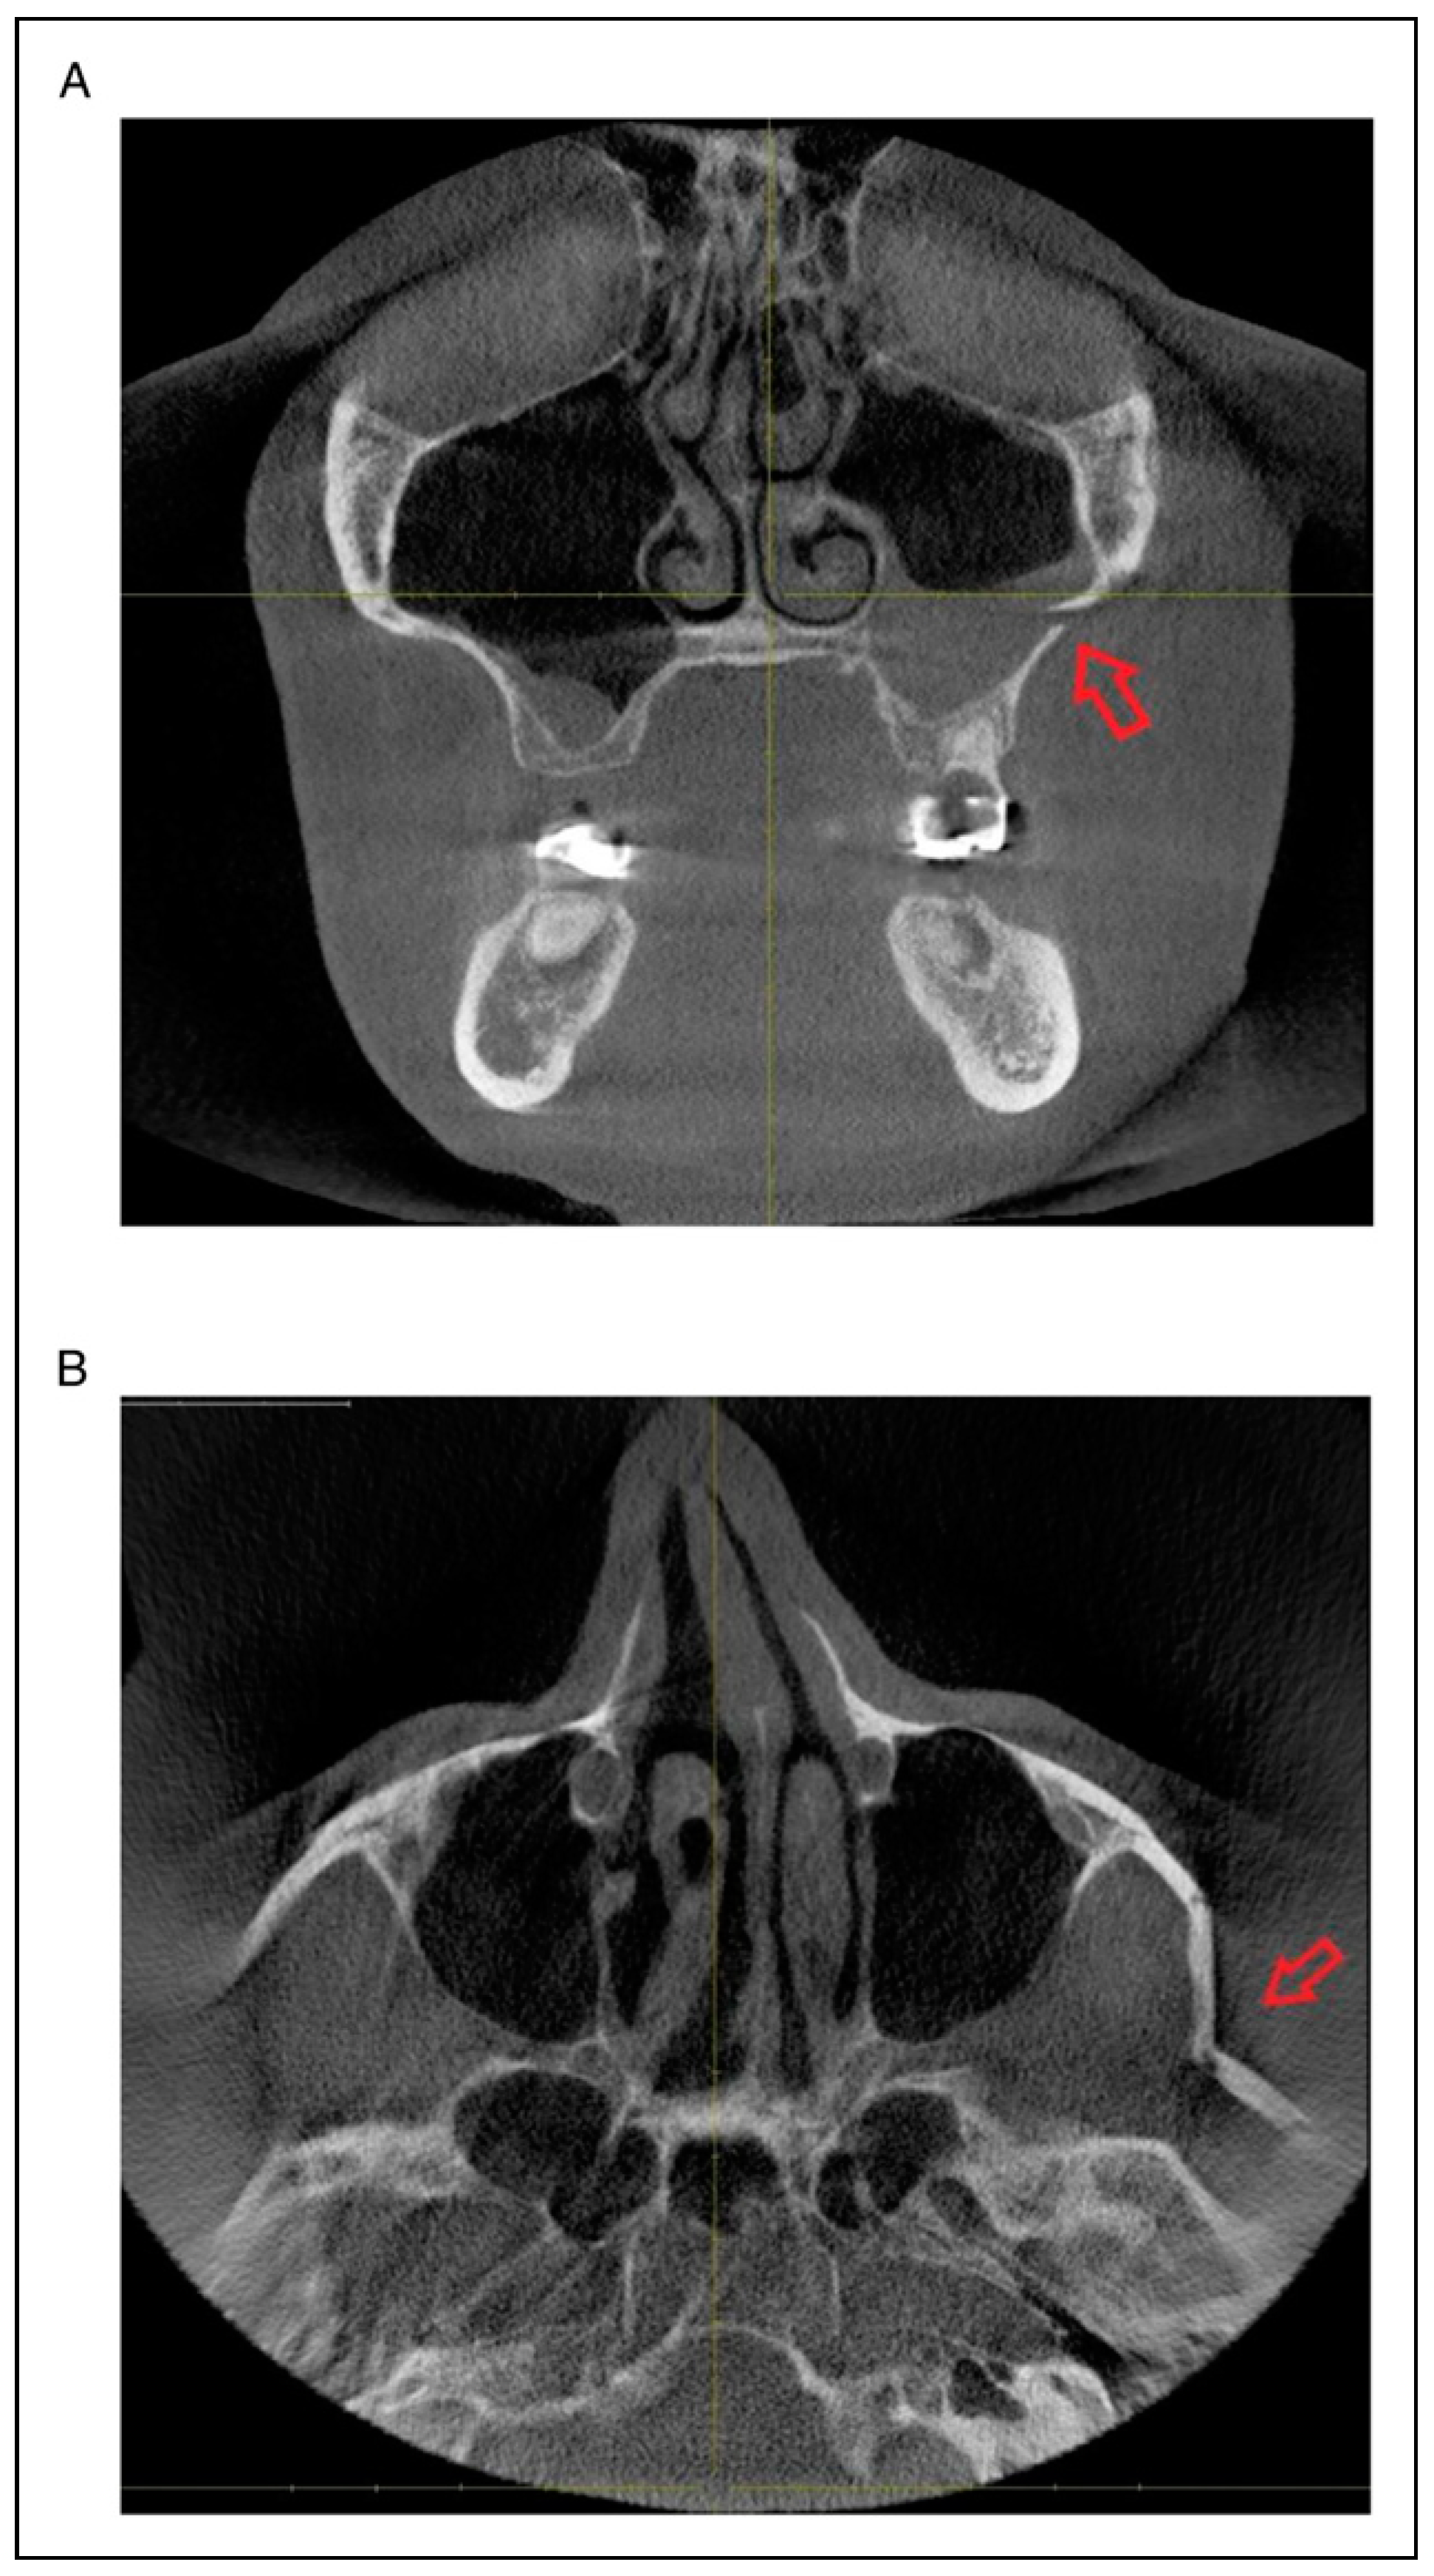

- Fracture location according to the anatomic sutures of the zygoma

- Radiologic involvement of maxillary sinus wall and paranasal buttress fractures.

Patterns of ZMO Fractures Regarding the Anatomic Sutures of the Zygoma

- Unisutural fracture (isolated fracture of a single anatomic suture of the zygoma):

- Zygomaticomaxillary suture (ZM)

- Infraorbital rim (IOR)

- Zygomaticofrontal suture (ZF)

- Zygomaticosphenoidal suture (ZS)—the anterolateral orbital floor

- Zygomaticotemporal suture (ZT)

- Bisutural fracture with the following fracture line combinations: